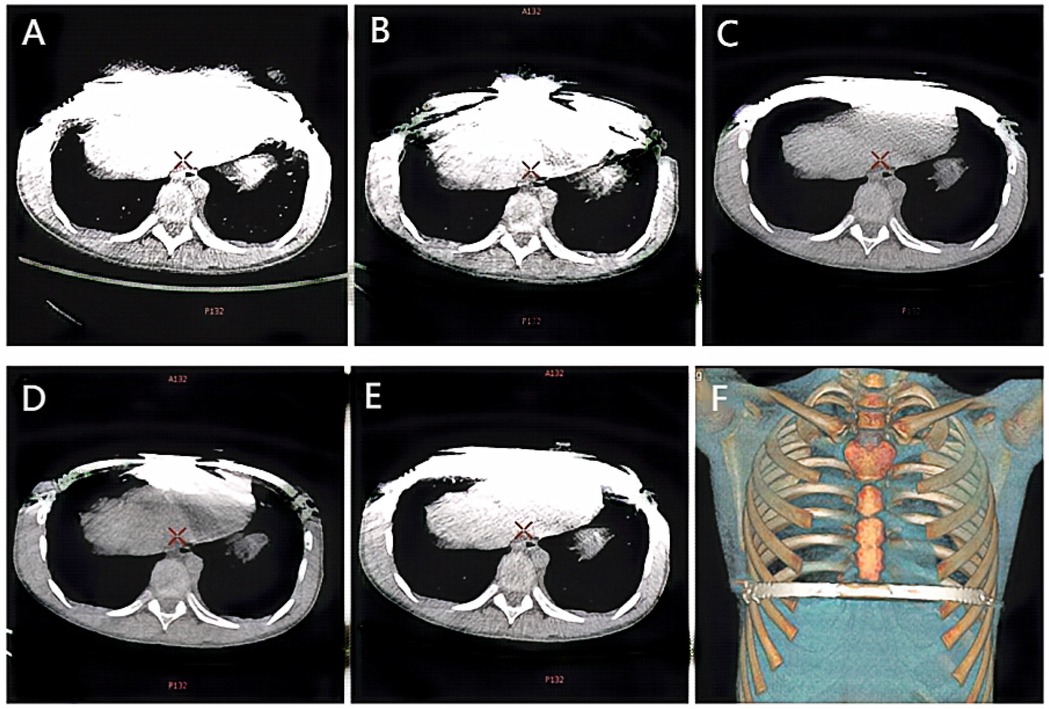

The scans were performed using the Gemstone Spectral Imaging (GSI) mode, which is characterized by rapid kV switching between 80 kVp and 140 kVp during a single scan acquisition. This provides the necessary paired low-energy and high-energy projection data. All images were reconstructed on an AW 4.6 workstation (GE Healthcare, Milwaukee, WI, USA). The raw spectral projection data were used to reconstruct virtual monoenergetic images (VMI) at 50 keV and 110 keV, a mixed-energy image simulating a conventional 120-kVp scan (120-kVp-like), and all series were reconstructed with a 1.25 mm slice thickness. This reconstruction process involves material decomposition (into water and iodine basis material pairs) followed by the synthesis of images representing the calculated linear attenuation at the desired monochromatic energy (keV). Subsequently, metal artifact reduction (MARs) processing was applied to generate the 50 keV + MARs and 110 keV + MARs image series. Figure 1 illustrates examples of the five reconstructed image series: (A) 50 keV, (B) 50 keV + MARs, (C) 110 keV, (D) 110 keV + MARs, and (E) 120 kVp-like.

Figure 1. Ct images of the same child under different scanning conditions. (A) 50 keV; (B) 50 keV + MARs; (C) 110 keV; (D) 110 keV + MARs; (E) 120 kVp-like; (F) Volume reconstruction (VR) image reconstructed from 120 kVp like image.